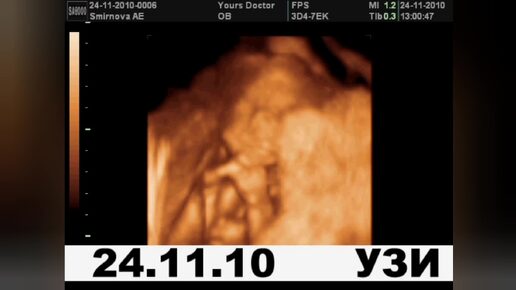

2010-11. Первая малышка